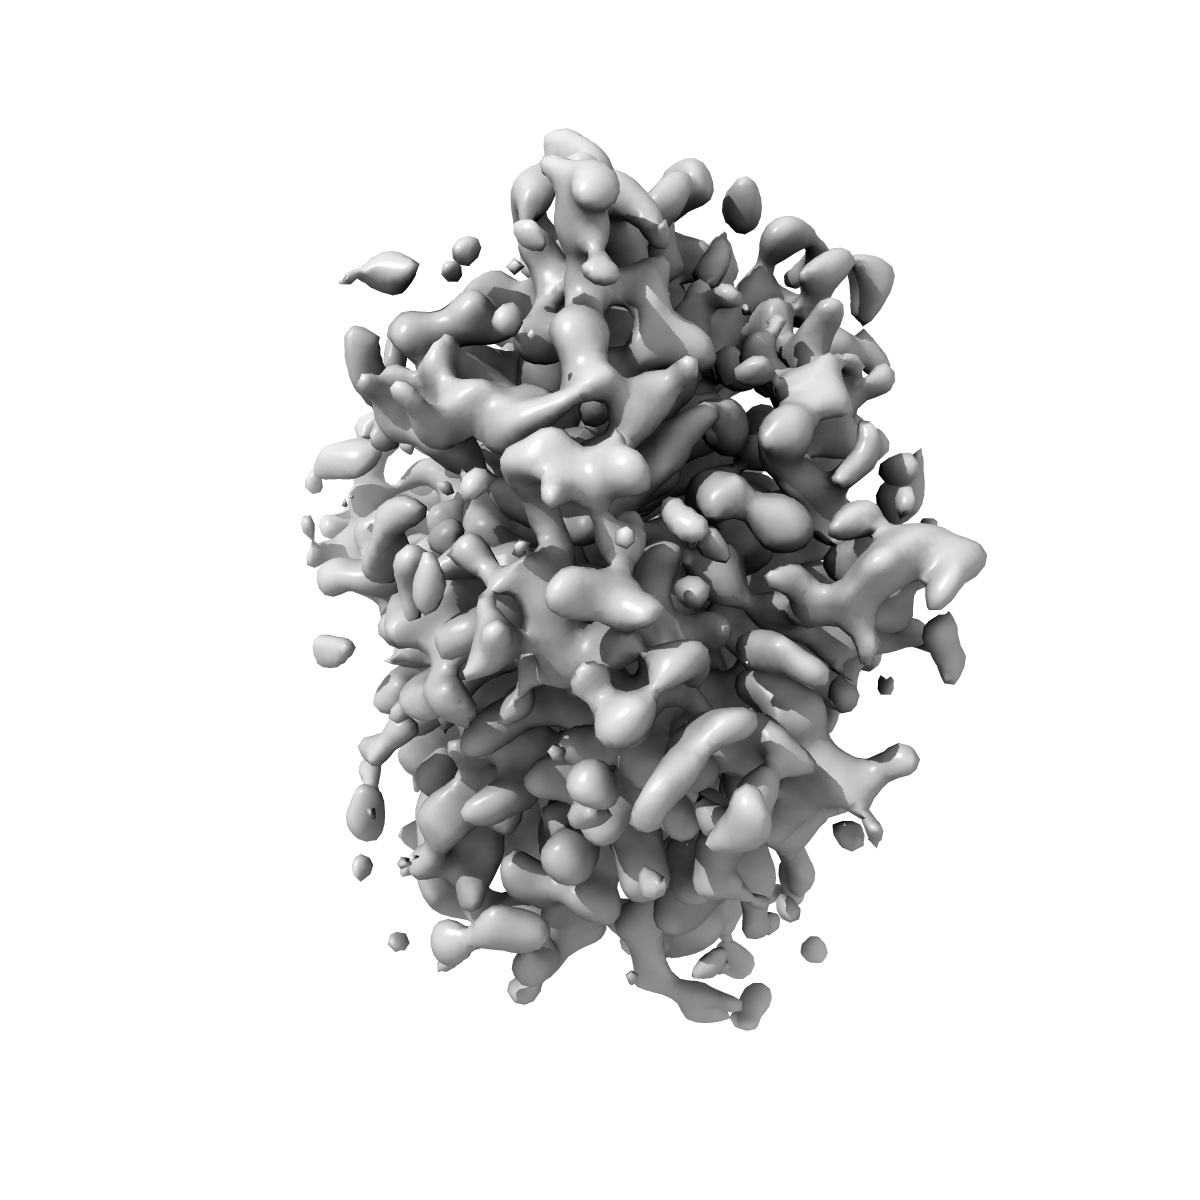

Structure of the human vesicular monoamine transporter 2 (VMAT2) bound to Tetrabenazine in an occluded conformation

Sample: Human VMAT2 complexed with Tetrabenazine

Structural mechanisms for VMAT2 inhibition by tetrabenazine.

Dalton MP , Cheng MH , Bahar I, Coleman JA

(2024) eLife , 12